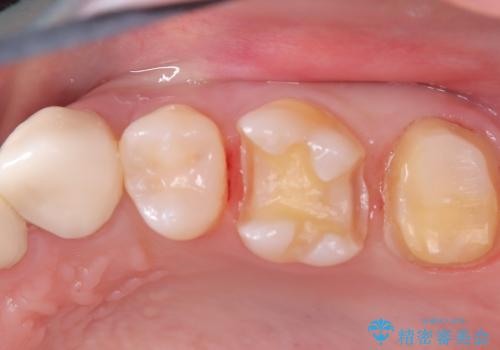

- 虫歯の治療を希望されました。一番奥の歯は虫歯が深かったことから神経を部分的に残す治療法(生活歯髄療法)や神経の治療(根管治療)についても説明し、治療介入をしました。

材料の特性を説明し、材質はどちらもセラミック、手前の歯は部分的な詰め物、奥の歯は被せ物での修復となりました。

左上7番は治療前の神経の検査では正常の範囲内の値を示しました。虫歯を削っていったところ神経まで到達したため、神経を部分的に残す治療法を選択しました。その後痛み等症状が出ず、また、神経の反応も正常であったため、被せ物にしています。